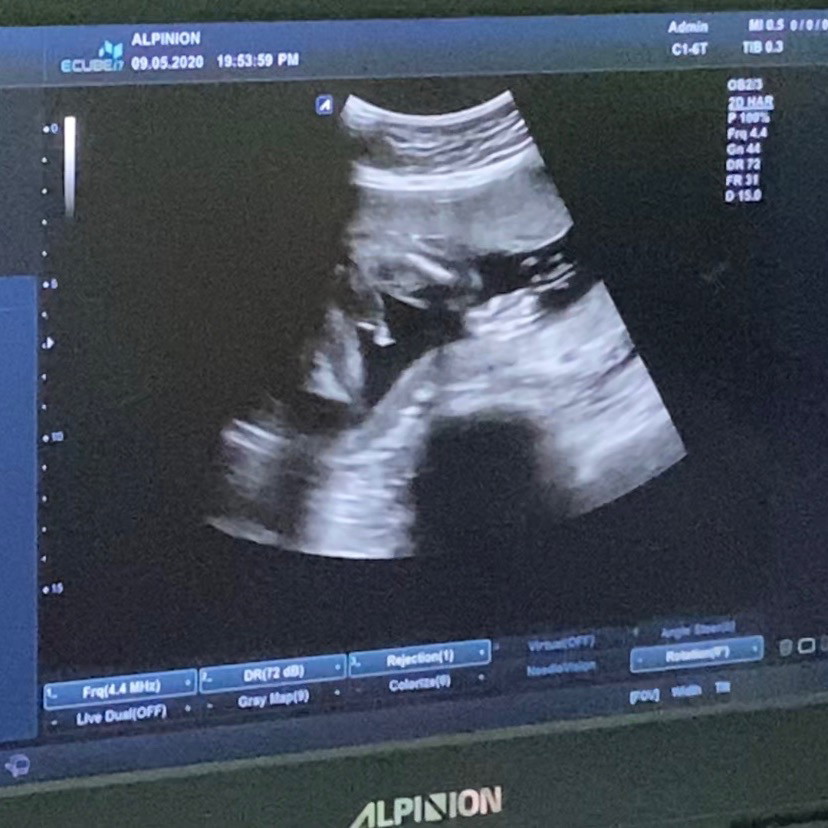

ในภาพเป็น ผช ใช่ไหมค่ะ พอดีหมอขอชัวร์ๆ เดือนหน้า เลยสอบถามแม่ๆ ที่มีประสบการณ์ลูกชาย หน่อยค่ะ ?ขอดูใบอัตตลาซาวเด็ก ผช . หน่อยจร้าาา? ถาพไม่ชัดเพราะถ่าย VDO มาจร้า ??

ผช.จ้า

ชายจร้า